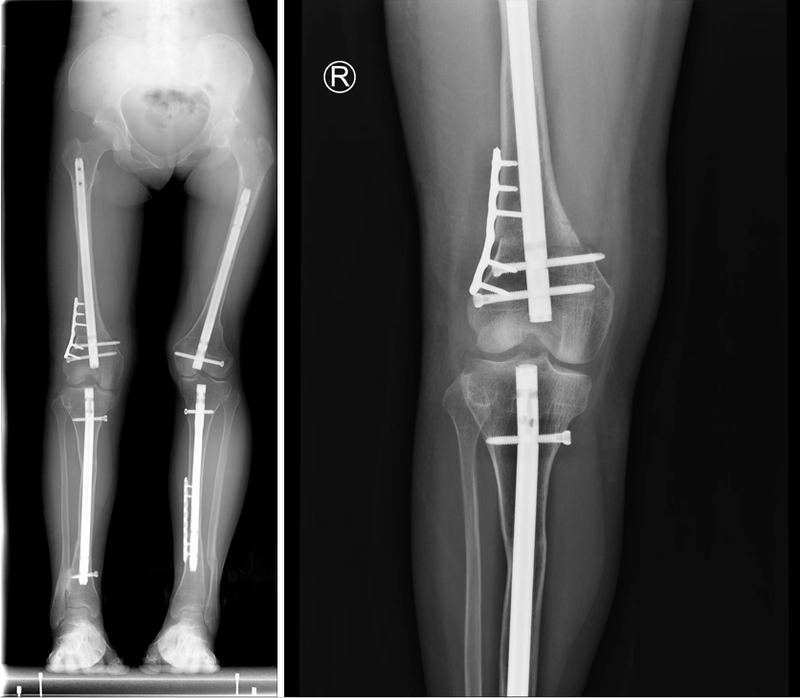

治療前成人成骨不全癥患者骨骼畸形矯正困難,軟組織攣縮嚴重,骨骼發(fā)育差,髓腔封閉。截骨后愈合困難。聯(lián)合外固定支架分期手術可以有效的解決這一難題治療中先利用外固定支架矯正攣縮的畸形然后再進行髓內固定手術治療后治療后3年畸形獲得糾正,恢復正常行走功能